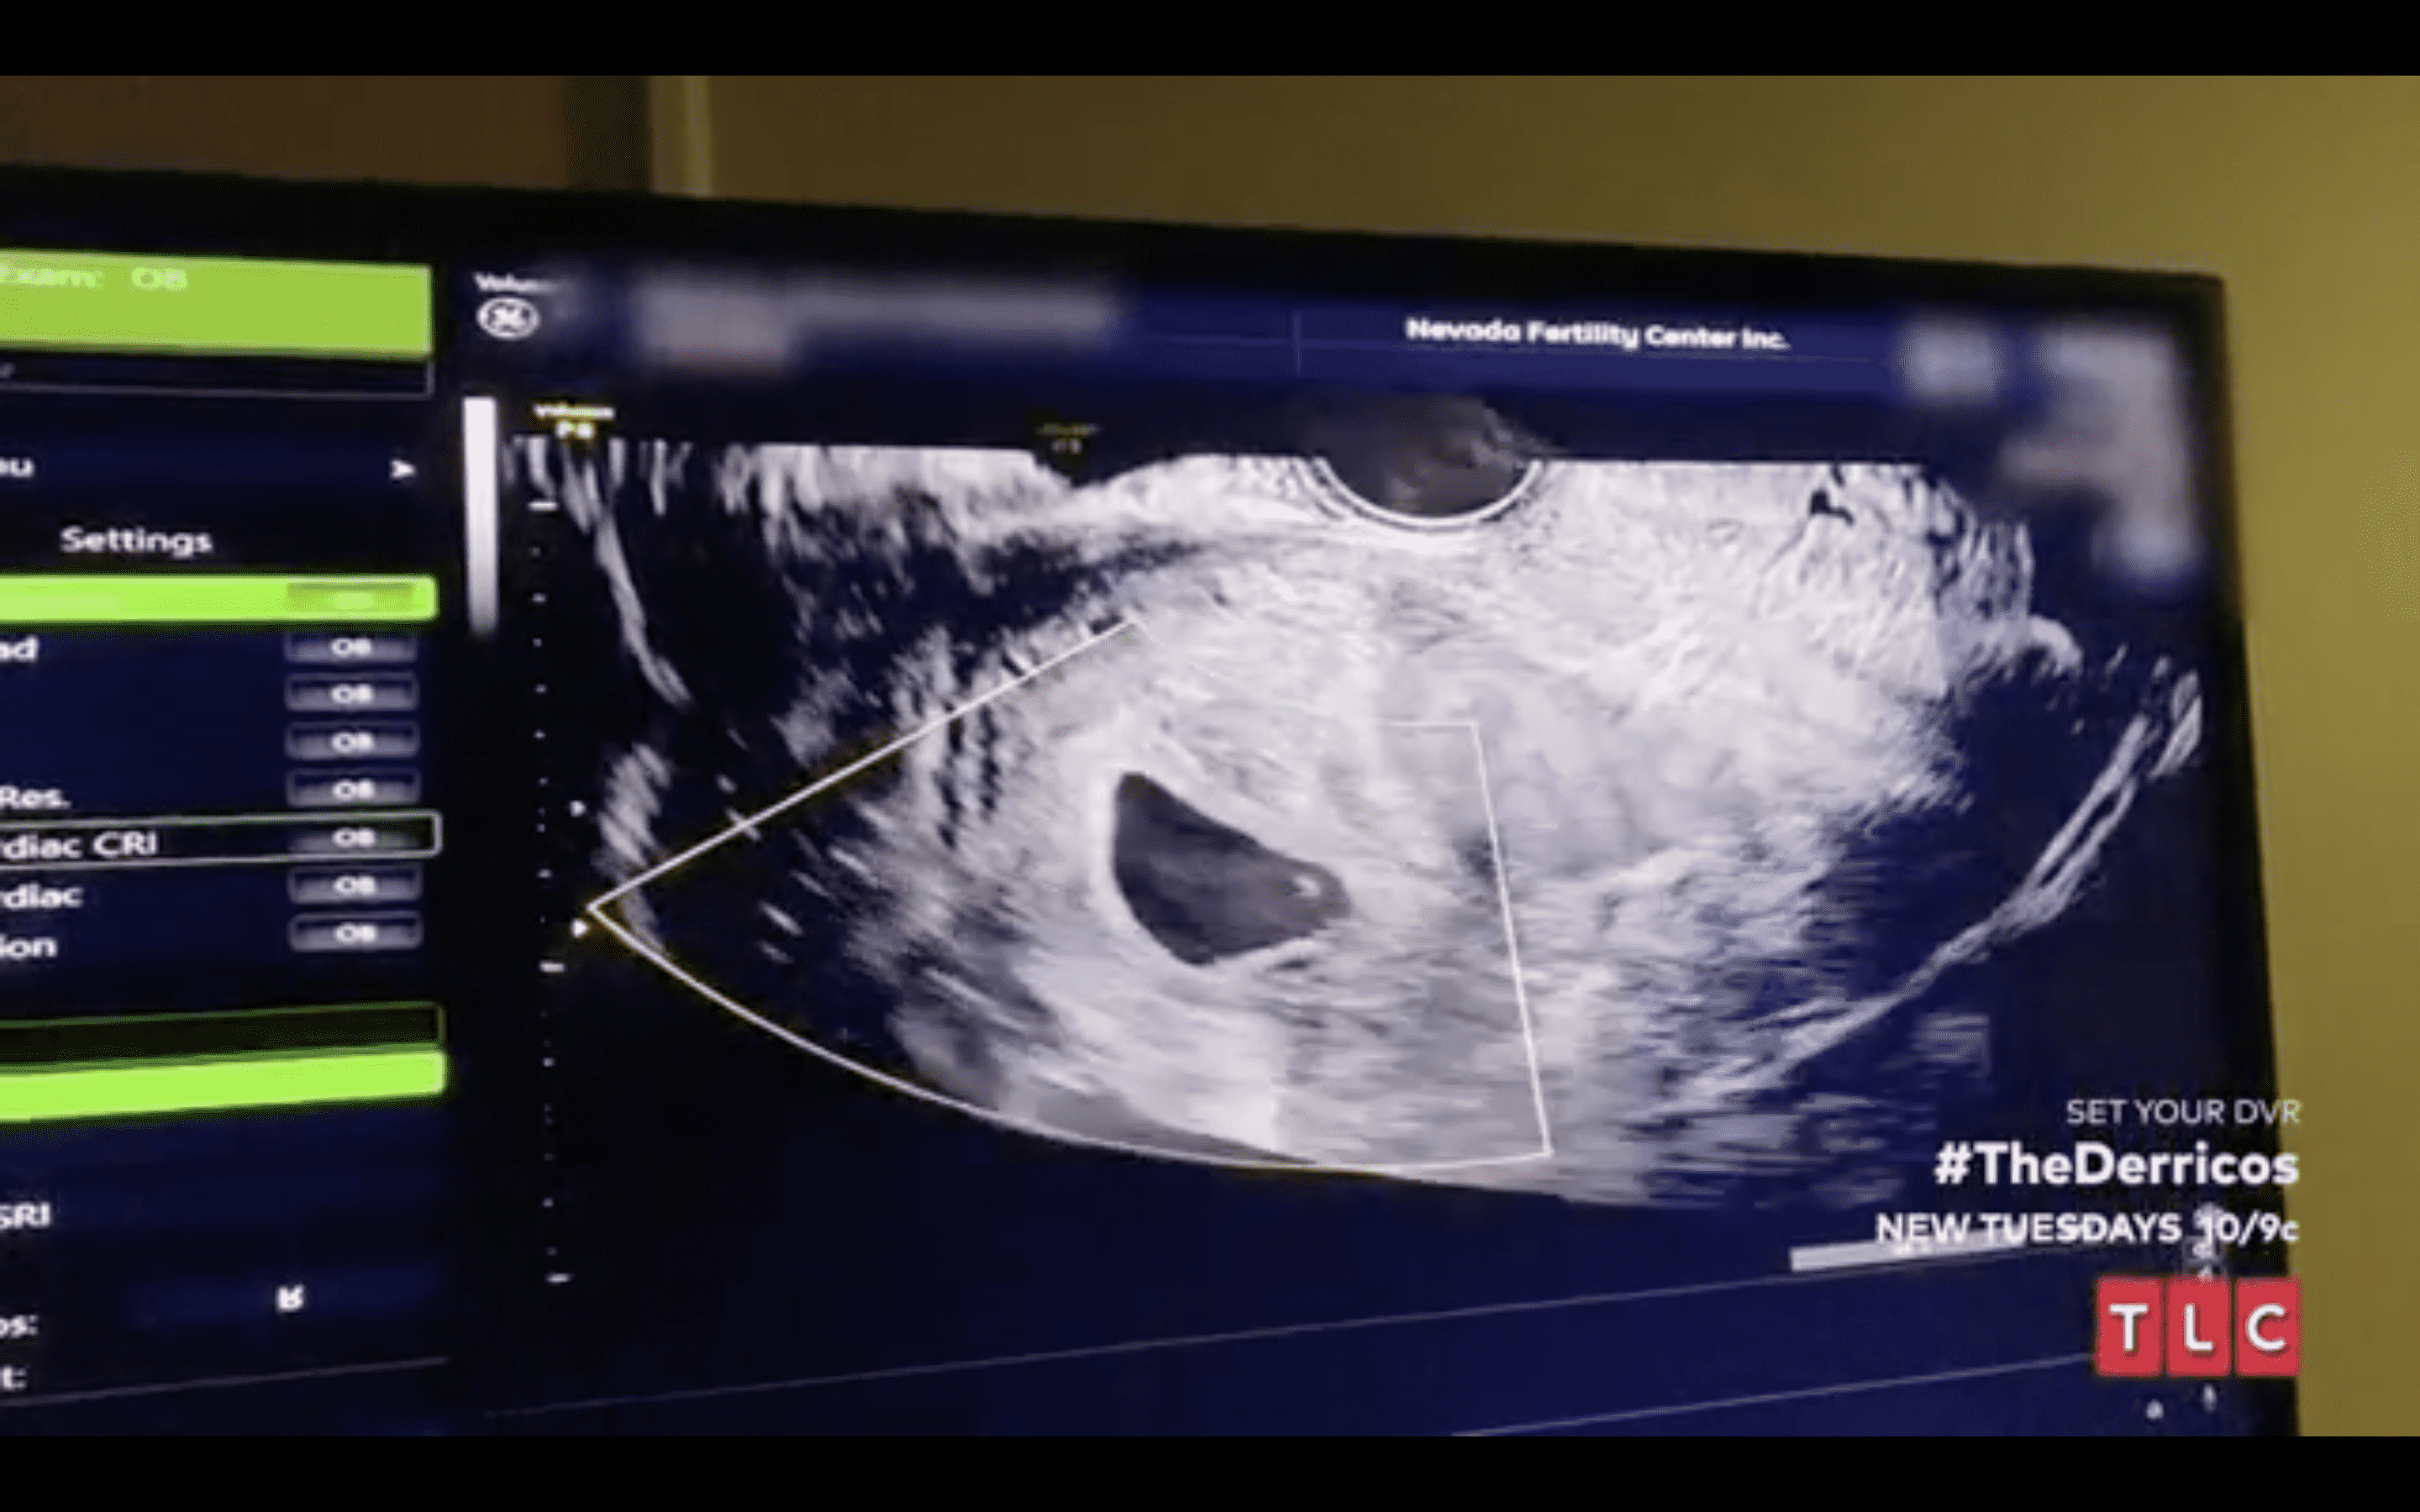

Despite hearing from her doctors that everything was fine with her pregnancy, a very anxious Karen felt that something wasn't right in her body. So she decided to get an ultrasound done just to put her anxiety to rest. Sadly, during the ultrasound, the doctor couldn't see anything or hear a heartbeat, turning Karen's worst nightmare into reality. Karen immediately began feeling over the edge on learning that she had a seventh miscarriage. As she began grieving for her loss, several fans took to Twitter to remind Karen that her family was already blessed with 14 children and her body needed rest.